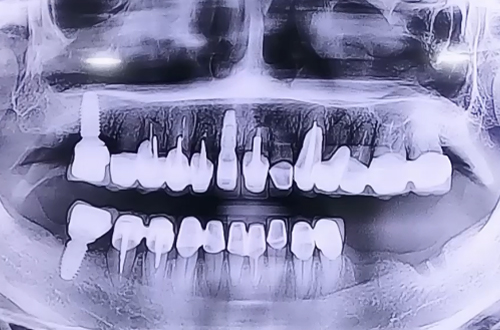

AFTER

발치되어 있는 부분의 잇몸이 많이 내려가 있는 케이스로 임플란트를 심으면서 눌릴 가능성이 높아 신경 바로 위까지만 임플란트를 심고 나머지 부위들은 주변으로 뼈이식을 병행하여 꼼꼼하게 진행해 드렸습니다.

신경 바로 위쪽으로 임플란트 두 개를 안전하게 심으며 양쪽 임플란트를 브릿지 형태로 왼쪽 아래 보철을 완성 시킬 계획입니다.

주변에 뼈이식하신 뼈들이 단단하게 굳는 기간을 기다리셨다가 위 쪽으로 머리 부분 보철을 올리실 때 다음 진료일지로 찾아뵙도록 하겠습니다. ^^!